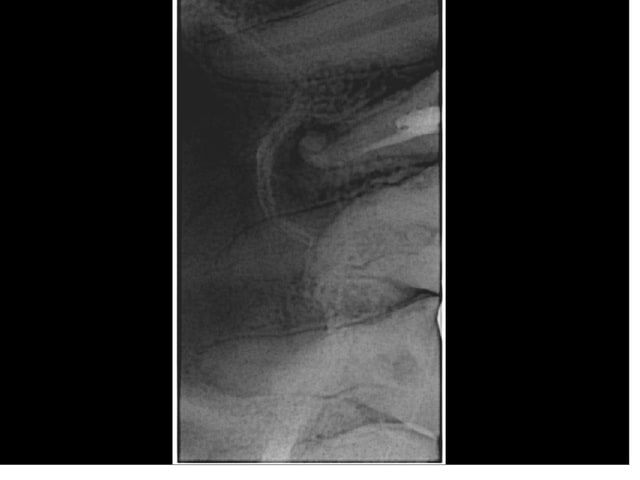

"Je comprends pas docteur ça a été fait ya 1 an à peine"

Bon c'est mieux mais apex très très très large...J'ai risqué mon gutta condensor à LT-5mm. Diamètre du cône à l'apex : 55/100ème. Je ne pense pas que ça soit très étanche (en direction distale en particulier) mais toujours mieux.